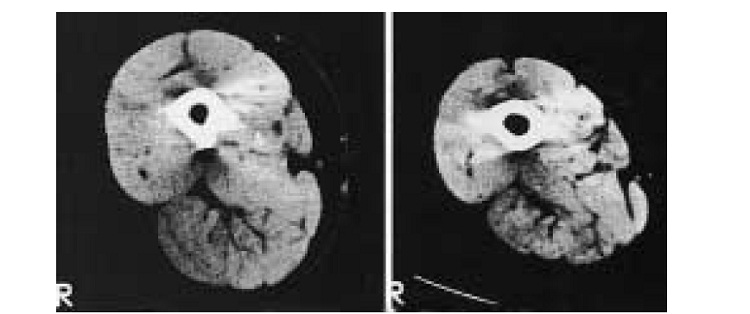

Figure.2 : Tomographie assistée par ordinateur d’un sujet sain (à gauche) et d’un sujet atteint de BPCO (à droite) appartenant au même groupe d’âge. [20]